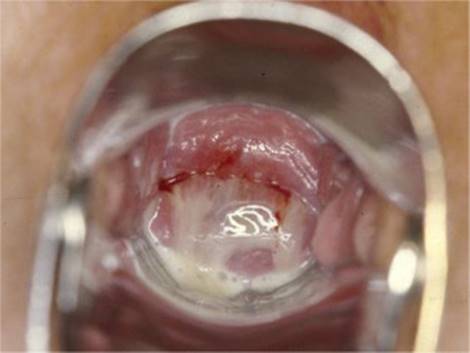

Vajinanın doğal ortamında Lactobacillus adı verilen yararlı bakteriler çoğunluktadır ve bu bakteriler, vajinanın asidik bir ortamda kalmasını sağlar. Ancak bazı durumlarda; özellikle cinsel ilişki, stres, antibiyotik kullanımı veya aşırı hijyen ürünlerinin kullanımı gibi nedenlerle vajinadaki iyi bakterilerin sayısı azalır ve yerine zararlı bakteriler çoğalır. Bu durumda kötü koku, gri-beyaz renkli ince bir akıntı oluşur ve bu da bakteriyel vajinozis belirtileridir. Tedavisi antibiyotiklerle yapılır, ancak tekrar etme olasılığı yüksektir. Bu yüzden vajina dengesini koruyacak şekilde hijyen alışkanlıkları oluşturmak çok önemlidir.

Bakteriyel vajinozis (BV). Görsel kaynağı: drkutaybiberoglu.com